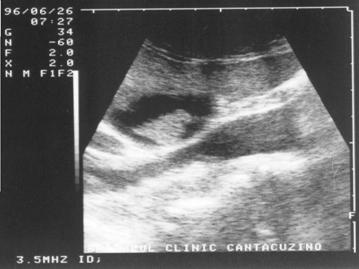

UMBRA ACUSTICA (CONUL DE UMBRA)

Este expresia unei atenuari si a unei reflectari maximale si apare in toate situatiile in care fasciculul de ultrasunete intalneste o structura foarte densa cum ar fi osul sau calculii. Distal de acesta nu mai exista ultrasunete, aspectul final fiind acela al unei "non imagini"; lipsa de ecouri se prezinta ca o structura liniara, de culoare neagra, denumita "con de umbra posterior".

Figura 18. Con de umbra in litiaza renala

Figura 19. Con de umbra posterioara in litiaza biliara